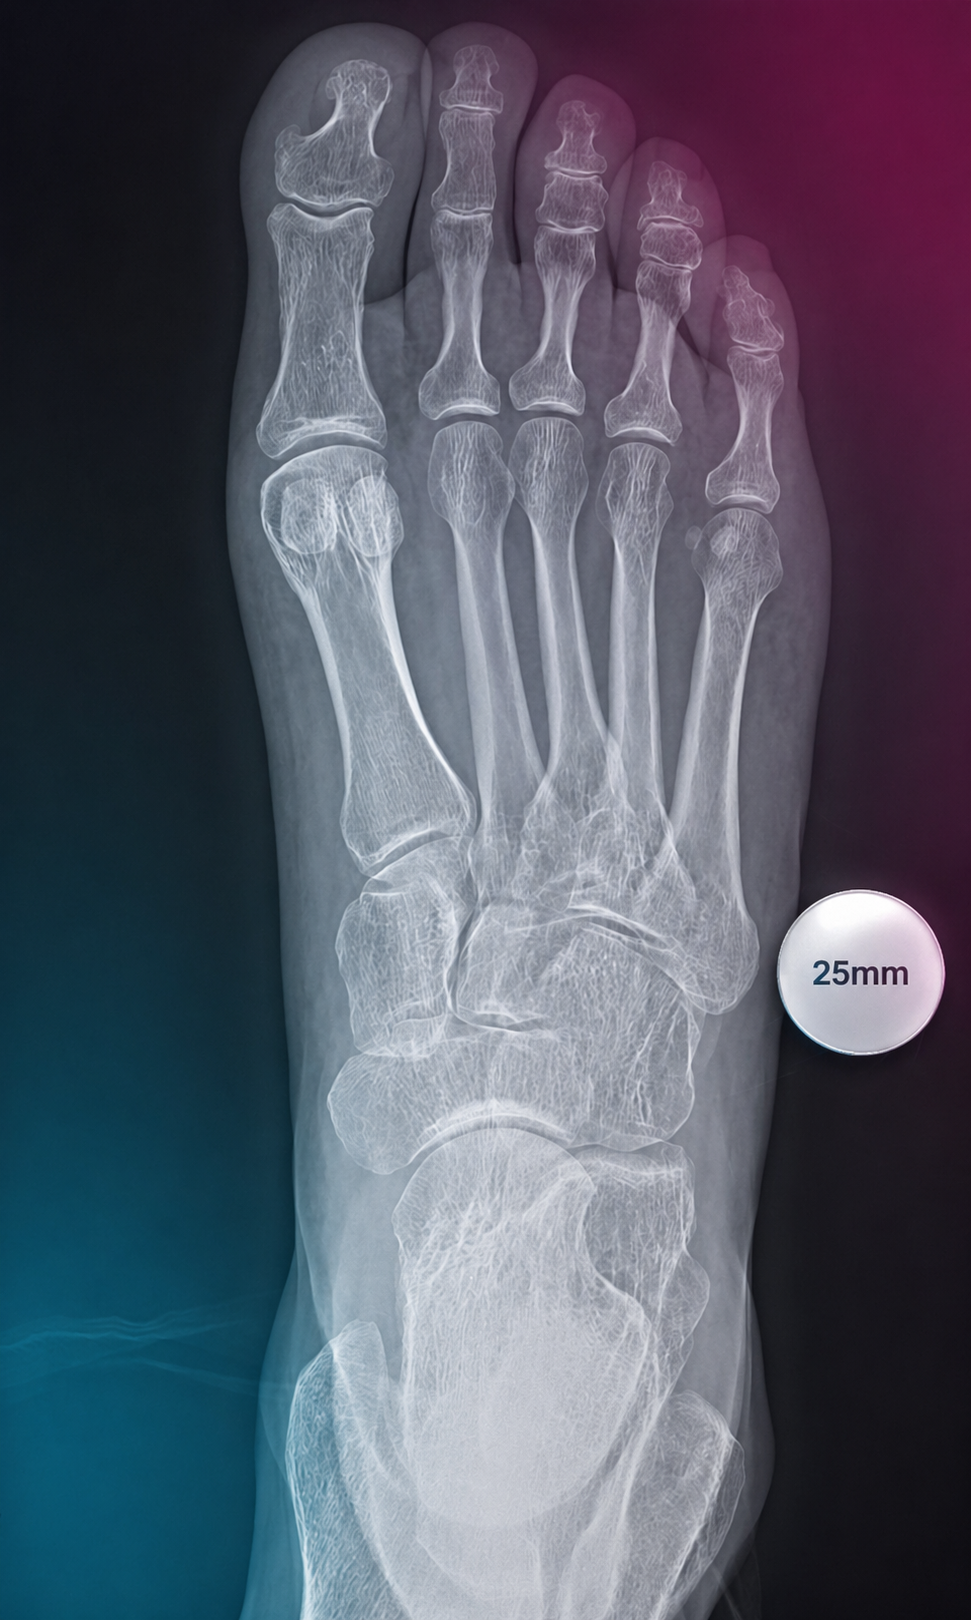

A compact guide for radiology teams on correct calibration sphere placement in orthopedic X-ray imaging. The marker must be positioned in the anatomical plane of the target joint so that digital scaling, measurements and preoperative templating remain clinically reliable.